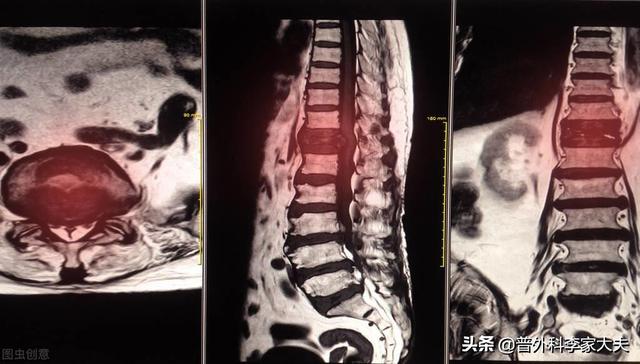

Sur le site des métastases osseuses, étant donné que le tissu osseux normal est détruit et remplacé par du tissu tumoral et que les cellules tumorales prolifèrent constamment, des ombres de masses de tissus mous peuvent être observées sur de nombreux sites de métastases osseuses, et peuvent être palpées si la masse se trouve dans une zone superficielle. En outre, l'érosion du tissu osseux normal par le tissu tumoral entraîne également la destruction et l'affaiblissement de la structure osseuse normale, de sorte que des fractures peuvent se produire sous l'effet de forces externes normales, appelées fractures pathologiques (figure ci-dessous). Outre la douleur et la fracture pathologique, les métastases au niveau de la colonne vertébrale peuvent également se manifester par une compression des racines nerveuses de la colonne vertébrale avec des symptômes tels qu'une déficience sensorielle, une faiblesse musculaire et, dans certains cas, une hypercalcémie.

Montrant un cancer avec métastases osseuses survenant dans la colonne vertébrale thoracique

Un homme de 46 ans a été vu en consultation pour une douleur persistante dans le bas du dos. On pensait que cette douleur était due à une hernie discale. Une radiographie a été effectuée et n'a révélé aucune anomalie. Les métastases osseuses provoquant une légère destruction osseuse sont invisibles à la radiographie, de même qu'une hernie discale. Je n'ai donc pas particulièrement pensé à la possibilité d'une métastase. Une semaine plus tard, comme il n'y avait toujours pas d'amélioration, il est venu passer un scanner et a découvert qu'une vertèbre lombaire avait été rongée. En voyant une telle image, le médecin spécialiste de l'imagerie a dû penser à la possibilité de métastases et a suggéré au patient de passer un scanner du thorax, et effectivement, il y avait une masse dans les poumons, qui a été considérée comme une métastase osseuse d'un cancer du poumon, ce qui a été confirmé par la pathologie plus tard.